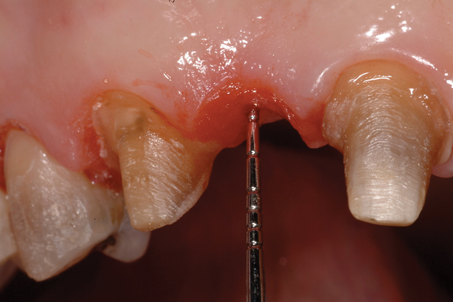

(10.) Close-up view of the existing edentulous tooth No. 10 site prior to the creation of the ovate pontic site.

Figure 10

A patient presented with two defective 3-unit fixed partial dentures spanning teeth Nos. 6 through 8 and teeth Nos. 9 through 11 (Figure 7). The defective fixed partial dentures were removed (Figure 8), an impression was made, and traditional provisional fixed partial dentures without ovate pontics were placed. After the impression was sent to the laboratory, the lab technician prepared ovate pontic sites on the stone cast (Figure 9) and fabricated the new definitive bridges. On the day of insertion, the provisional fixed partial dentures were removed (Figure 10), ovate pontic sites were prepared using a teardrop-shaped diamond bur (Figure 11), and the sites were sounded to confirm that there was at least 2 mm from the base of the pontic site to the alveolar bone (Figure 12). The fixed partial dentures were cemented, and the postoperative healing was uneventful (Figure 13).